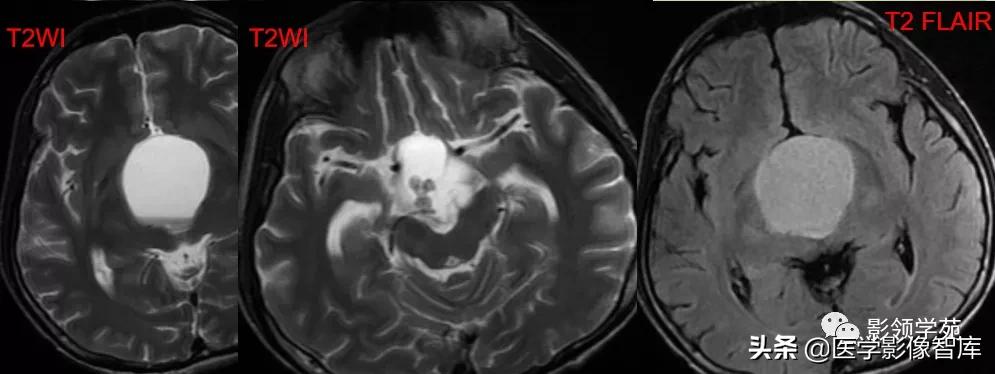

男,2岁,双视力障碍

鞍区见一类圆形囊性肿块,呈长T1长T2信号,囊壁厚薄不均。

囊壁呈环状强化,囊内未见明显强化。病灶占据蝶鞍、鞍上池及第三脑室前部,边缘清楚。

鞍区见一类圆形囊性肿块,囊壁呈蛋壳样钙化。肿块向下压入蝶鞍,向上达到第三脑室水平。